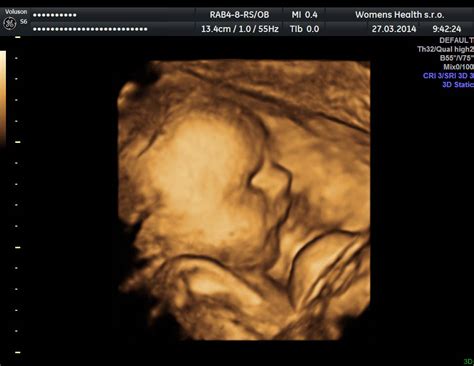

3D a 4D Ultrazvuk: Pohľad na Bábätko Zblízka

3D a 4D ultrazvuk predstavujú špeciálne zobrazenia, ktoré umožňujú rodičom vidieť dieťatko v trojrozmernom obraze. 4D ultrazvuk navyše zobrazuje pohyb dieťaťa v reálnom čase, čo umožňuje vidieť, ako sa usmieva, zíva či hýbe. Tieto vyšetrenia sú obľúbené pre možnosť získať realistický obraz dieťaťa, vrátane jeho čŕt. Lekár môže z takéhoto vyšetrenia vytlačiť aj 3D fotografiu. Hoci tieto metódy nie sú vždy zreteľné a "vydarené", pre mnohé nastávajúce matky predstavujú nezabudnuteľný zážitok.